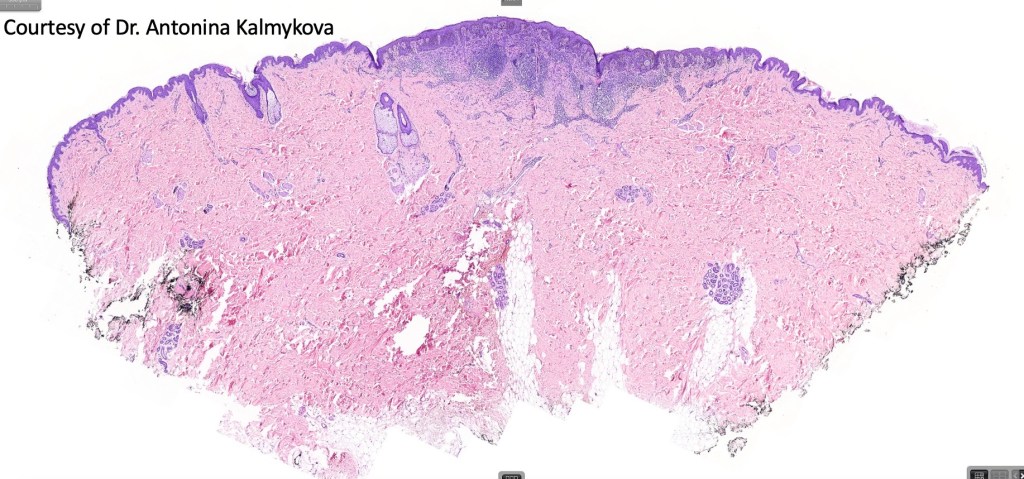

Combined congenital & blue nevus (same case as the clinical photographs coursty of Dr. Antonina Kalmykova